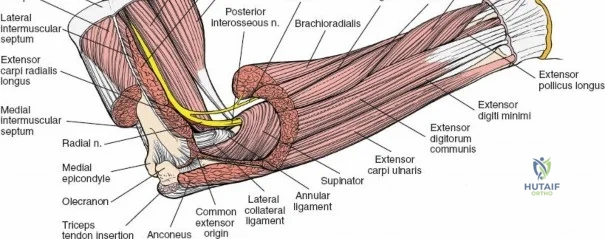

The Internervous Planes of the Forearm

The anterior approach to the radius is an elegant example of utilizing true internervous planes to achieve deep exposure without denervating musculature. Distally, the internervous plane lies between the brachioradialis muscle (innervated by the radial nerve) and the flexor carpi radialis muscle (innervated by the median nerve). Proximally, the plane transitions to lie between the brachioradialis (radial nerve) and the pronator teres muscle (median nerve). Exploiting this plane allows the surgeon to mobilize the entire lateral muscular compartment (the "mobile wad" comprising the brachioradialis, extensor carpi radialis longus, and extensor carpi radialis brevis) away from the anterior flexor compartment.

The Posterior Interosseous Nerve (PIN)

The posterior interosseous nerve is the single most important structure left vulnerable during exposure of the proximal radius. A branch of the radial nerve, the PIN dives into the supinator muscle through the Arcade of Frohse. It travels obliquely and spirally around the radial neck and proximal shaft within the substance of the supinator. In approximately 25% of patients, the nerve comes into direct contact with the posterior periosteum of the radial neck. Therefore, any blind placement of retractors around the posterior aspect of the proximal radius is strictly contraindicated, as it can easily crush the nerve against the bone, resulting in devastating loss of finger and thumb extension.

Vascular Anatomy and the Recurrent Radial Leash

The radial artery runs distally through the forearm, initially lying deep to the brachioradialis muscle before becoming more superficial in the distal third. Just distal to the elbow joint, the radial artery gives off a complex network of vessels known as the recurrent radial artery leash (the "leash of Henry"). These vessels branch laterally to supply the brachioradialis and the mobile wad. To successfully mobilize the brachioradialis laterally and access the proximal radius, this entire leash of vessels must be meticulously isolated, ligated, and divided. Failure to do so will tether the brachioradialis, prevent adequate exposure, and risk severe postoperative hematoma from avulsed vessels.

Superficial Surgical Dissection and Internervous Plane

Incise the deep fascia of the forearm in line with the skin incision. The initial goal is to identify the medial border of the brachioradialis as it courses down the forearm. It is a common pitfall to search for this border too far laterally. At the level of the elbow, the brachioradialis is expansive and extends almost halfway across the anterior forearm. It is surprisingly easy to mistake the plane between the brachioradialis and the extensor carpi radialis longus for the correct intermuscular plane.

To confirm the correct plane, look for the superficial branch of the radial nerve. This sensory nerve runs on the undersurface of the brachioradialis muscle. Once the true medial edge of the brachioradialis is found, develop the plane between it and the pronator teres (proximally) or the flexor carpi radialis (distally). Retract the brachioradialis laterally, taking care to keep the superficial radial nerve attached to its undersurface to protect it from traction injury.

Exposing the proximal third of the radius requires extreme vigilance due to the proximity of the posterior interosseous nerve. The key anatomical landmark here is the insertion of the biceps tendon. Follow the biceps tendon distally to its insertion on the bicipital tuberosity of the radius. A small bursa lies just lateral to the tendon; incise this bursa to gain initial access to the proximal radial shaft. Because the radial artery lies superficial and medial to the tendon at this level, all deep dissection must remain strictly lateral to the biceps tendon.

The proximal radius is draped by the supinator muscle. The PIN passes directly through the belly of the supinator. To protect the nerve, the forearm must be fully supinated. Supination dynamically rotates the radius, carrying the insertion of the supinator anteriorly and simultaneously displacing the PIN laterally and posteriorly, safely away from the surgical field.